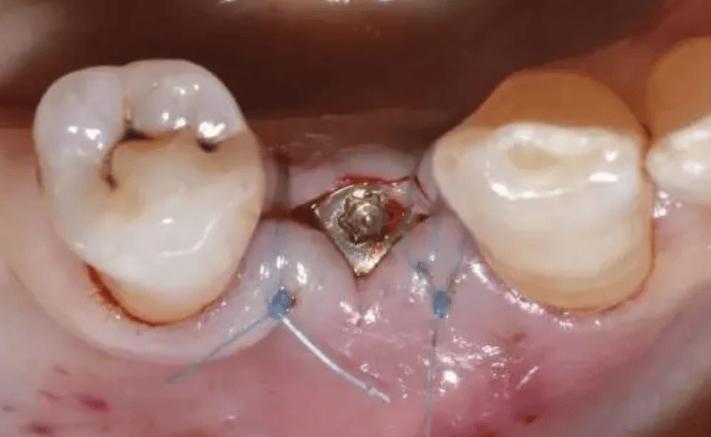

(图片来源网络,侵删)- 种植牙成功的关键在于种植体与牙槽骨之间形成牢固的骨结合,这个过程通常需要数月时间。